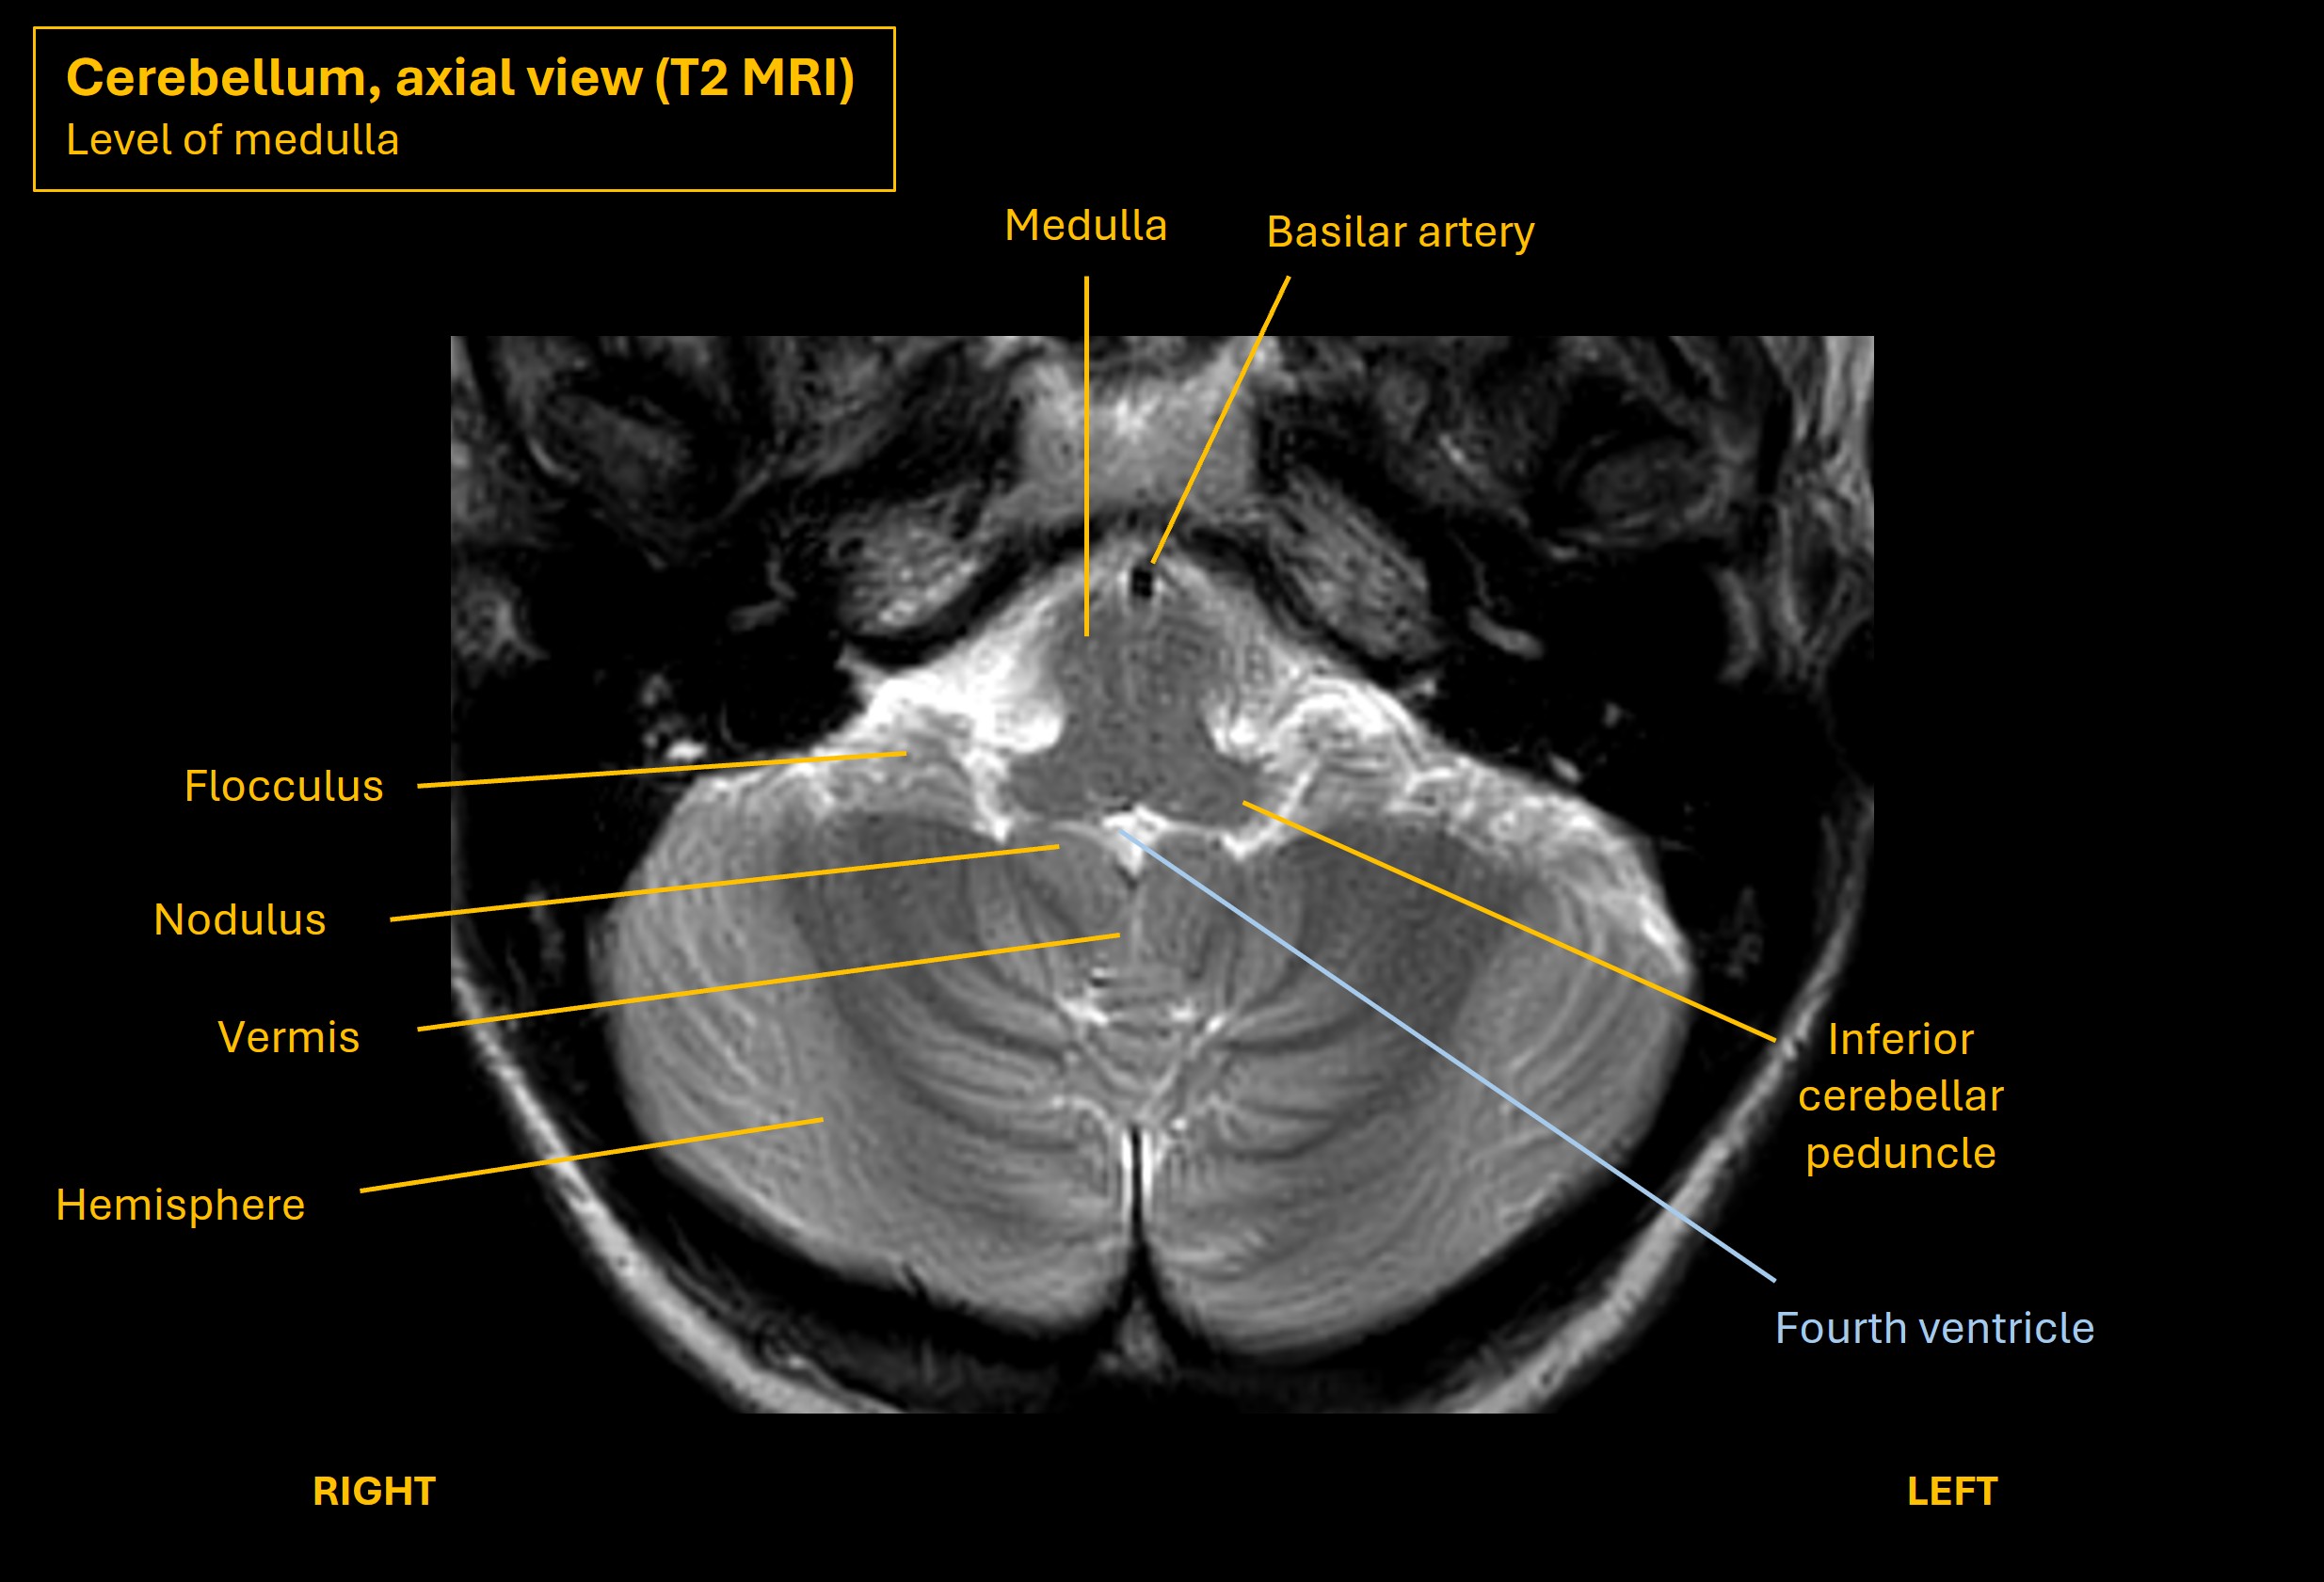

The images below show axial and sagittal views of the cerebellum and illustrate key features and relationships with the brainstem.

level of medulla

The vestibulocerebellum is made of the the flocculus (somewhat lateral) and nodulus (central, next to the vermis) - visible on the axial MRI images above at the level of the medulla. This is part of the inferior cerebellum. It has lots of afferent and efferent connections with the vestibular system and the eyes.